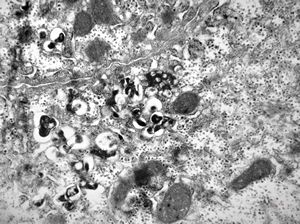

M,16y. | Wilson disease susp.